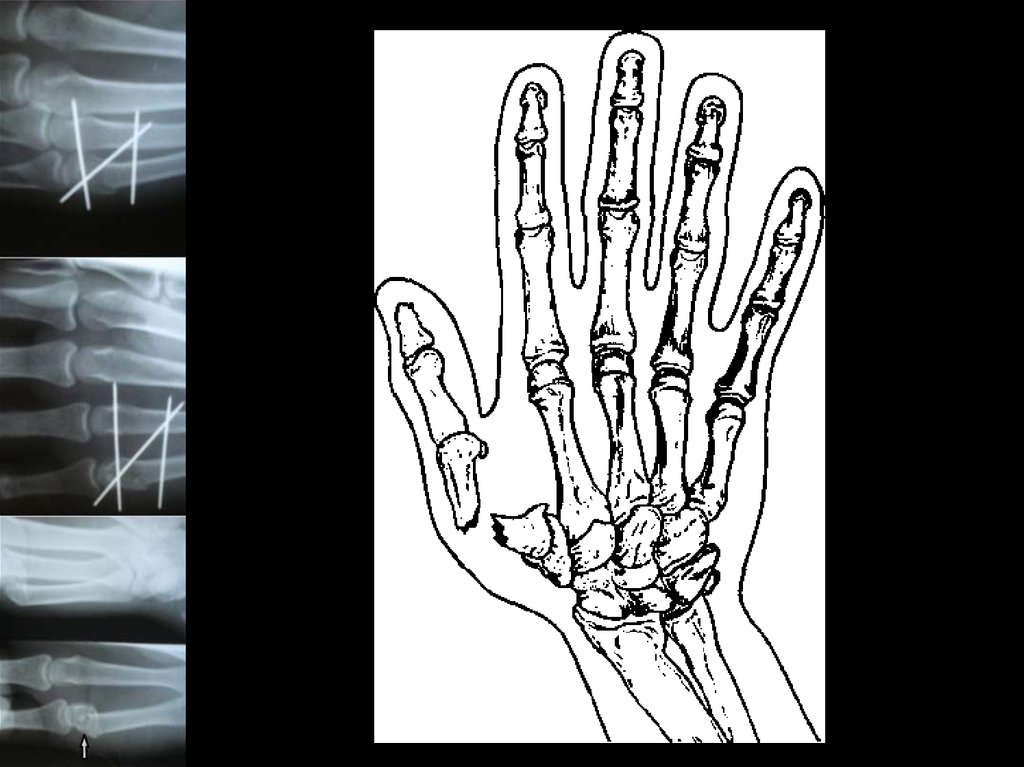

11.

12. Лечение переломо-вывихов основания 1 пястной кости стержневым аппаратом.